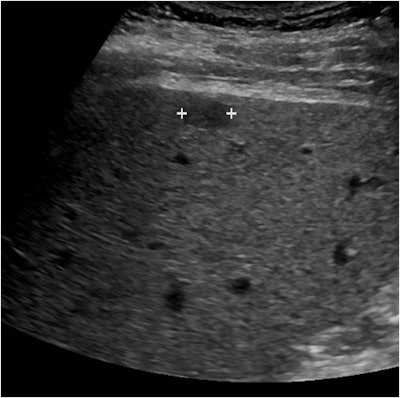

Of the 26 patients with MR findings of a mass-like area with arterial phase hyperenhancement only, 12 had a nodule on the baseline ultrasound scan that was not seen on MRI. Eleven of the 12 had classic HCC features on CEUS: arterial phase hyperenhancement and weak late contrast washout, she said. The other patient had classic nonhepatocellular carcinoma features on CEUS: arterial phase hyperenhancement and rapid contrast washout.